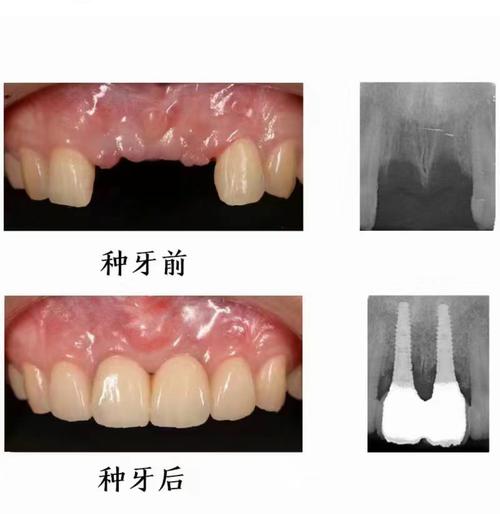

- 种植牙的本质: 种植牙是通过外科手术将人工牙根(种植体)植入牙槽骨中,待其与骨组织牢固结合(骨结合)后,再在种植体上安装牙冠,它模拟的是天然牙根的功能。